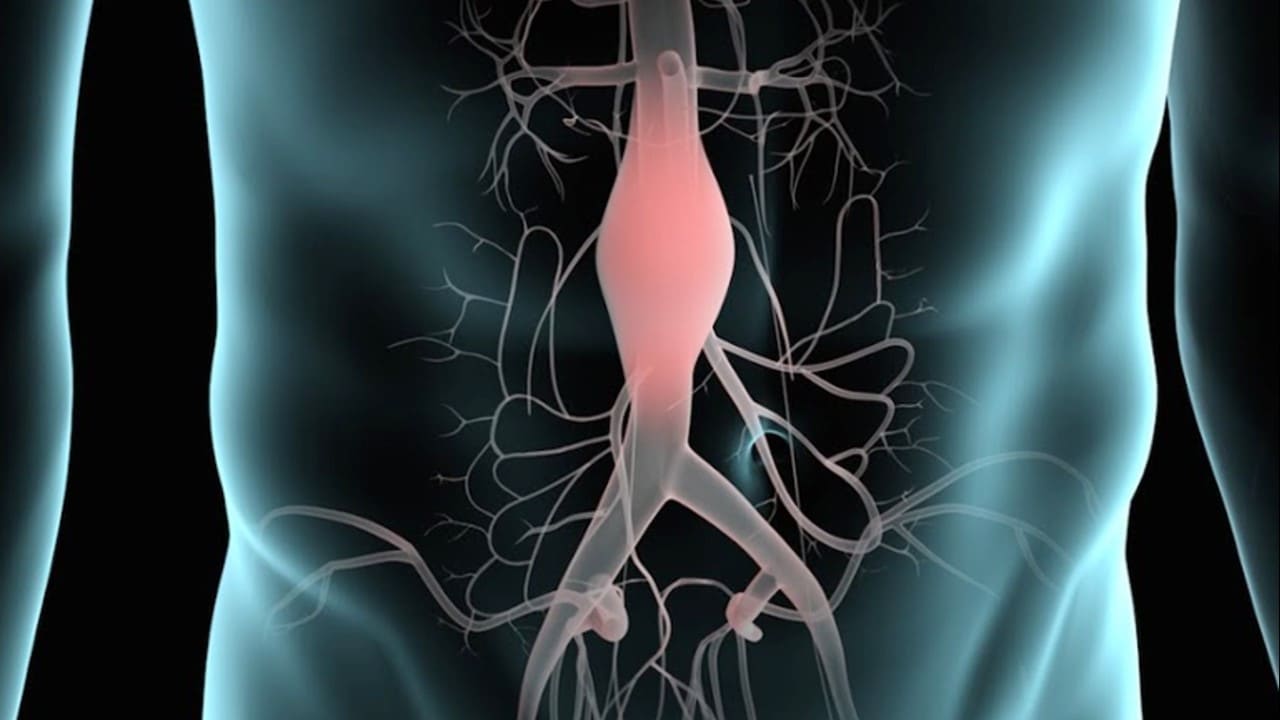

Un aneurisma aórtico abdominal es un agrandamiento de la parte baja de la aorta que se extiende a.

aneurisma de la aorta abdominal La aorta va desde el corazón hasta el. Recibe sangre con gran contenido en oxígeno. Cirugía vascularrupturas de aneurisma de la aorta abdominal: La cirugía de reparación abierta de aneurisma aórtico abdominal (aaa) se realiza para arreglar una parte dilatada de la aorta. Si tienes un aneurisma de la aorta abdominal en expansión, podrías notar lo siguiente: La incidencia de aaai en. En este artículo examen físico pruebas de detección y de diagnóstico ¿quiénes deben someterse a un examen de detección de aneurisma de aorta torácica? Los aneurismas aórticos aneurismas aórticos la aorta, que mide alrededor de 2,5 cm de calibre o diámetro, es la arteria más grande del cuerpo.